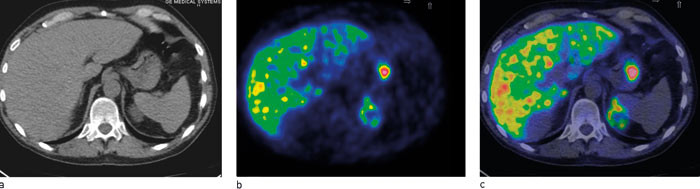

Metomidat er en 11C-merket enzymhemmer som blokkerer enzymet 11-betahydroksylase, et essensielt enzym i produksjonen av kortisol og aldosteron. For diagnostisk avklaring ved binyresvulster og binyrebarkkreft kan PET med 11C-metomidat anvendes når verken CT eller MR er tilstrekkelig for diagnostikk. Metomidat er blitt brukt til oppfølging av pasienter med tilfeldig påvist lesjoner (16) og maligne lesjoner i binyrebarken (22). Alle tumorer i binyrebarken, også binyrebarkcancer har vist meget høyt opptak av 11C-metomidat, og høyt opptak plasserer lesjonen i binyrebarken (22) – (24) (fig 3). Binyretumorer som tar opp 11C-metomidat er således enten benigne kortikale tumorer eller, i sjeldne tilfeller, binyrebarkcancer (22) – (24).